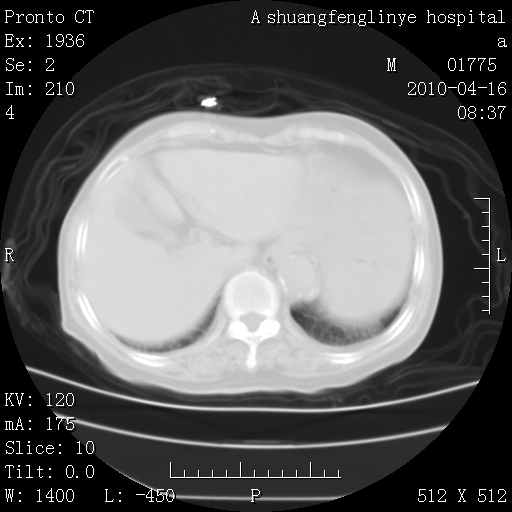

标题: CT25784:咳痰、请会诊!结核?

老年肺间质纤维化,肺动脉高压-----肺心病。

慢支肺气肿,左上陈旧性结核,主动脉冠脉钙化

1)左肺上叶结核(纤维、增殖病灶)。2)冠状动脉及主动脉钙化。

1)左肺上叶结核(纤维、增殖病灶)。2)冠状动脉及主动脉钙化。肺动脉高压